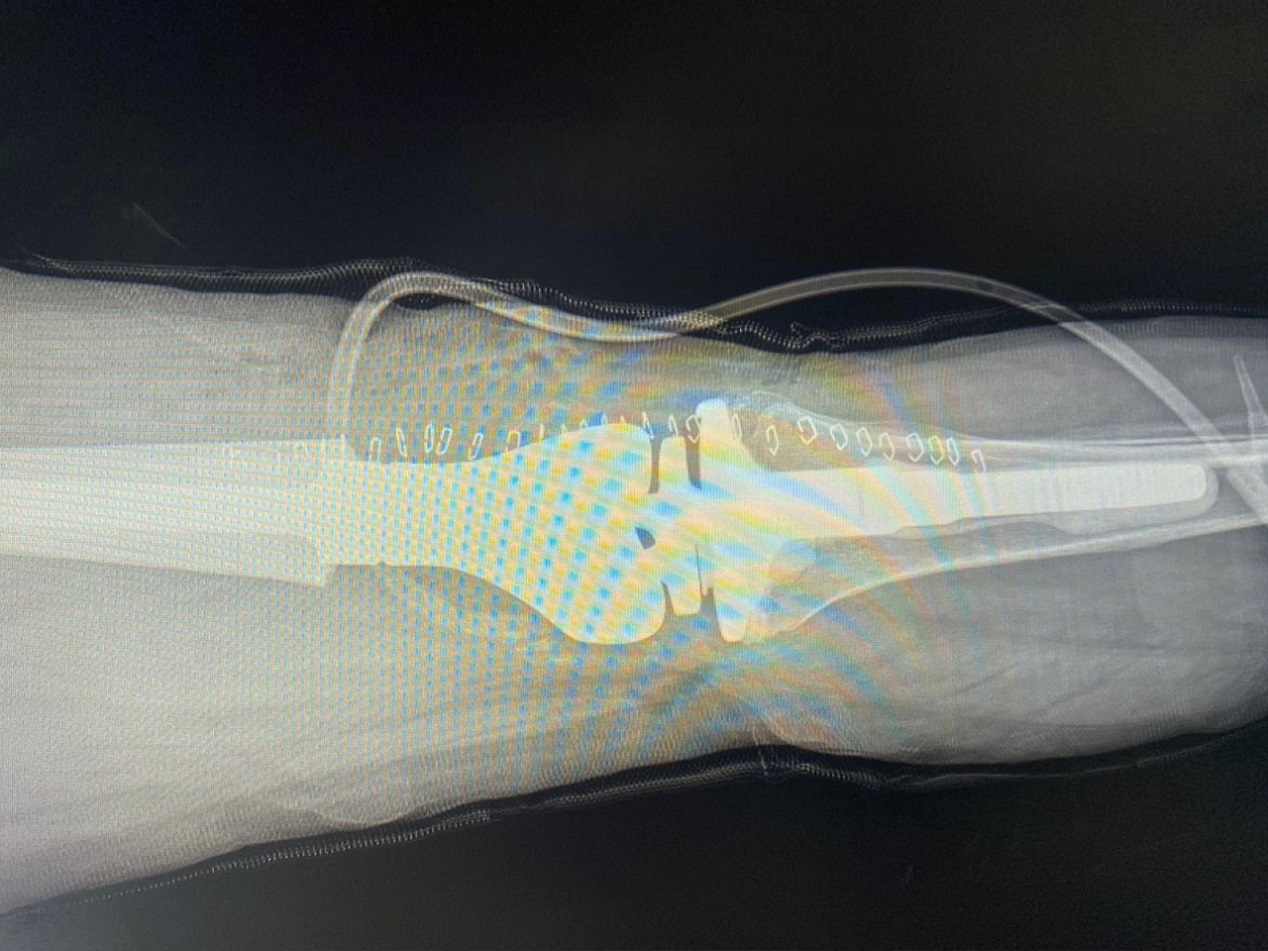

Recientemente, este centro asistencial, llevó a cabo con éxito su primera cirugía de revisión de prótesis de rodilla de este 2023. La intervención quirúrgica se realizó en una paciente de 63 años a la que se le colocó una prótesis tumoral.

"La paciente vino por un dolor en la rodilla izquierda en la que hace 9 años tuvo una sustitución con una prótesis que le fue colocada por un desgaste del cartílago articular. Le hicimos radiografías, una tomografía y documentamos un desgaste del implante con un desgaste del fémur distal, también se documentó rodilla de charcot", explicó el Dr. Soch.

"Tras el diagnóstico el equipo médico decidió realizar una revisión de la prótesis primaria que tenía la paciente y se le colocó una prótesis tumoral", agregó el profesional.